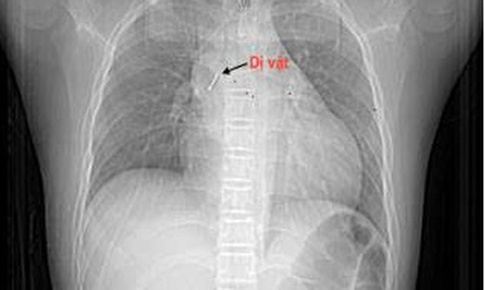

Camera bệnh viện - 22/10/2025 16:04SKĐS - Trong lúc vừa xem tivi vừa ngậm chiếc đinh ghim bảng, bé P (13 tuổi ở Hà Nội) không may mắc luôn dị vật này trong đường thở. Gia đình lập tức dưa trẻ tới cơ sở y tế để lấy dị vật.